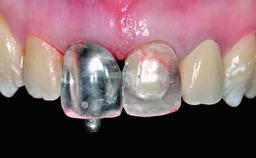

Replacement of an Ankylosed Upper Left Central Incisor: Bone Augmentation and Socket Grafting, Late Placement of an RC Bone Level Implant

Abutment Type CAD/CAM

Prosthesis Type FDP